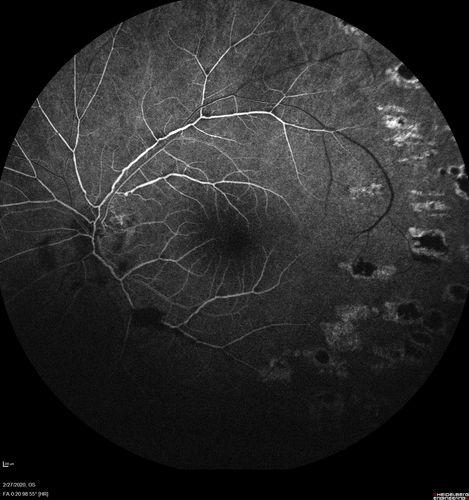

Eales Disease and fresh vitreous hemorrhage - 20 year old man

20 year old mane with fresh vitreous hemorrhage in the right eye.  At age 15 he had a PPV and laser in the left eye and laser in the right eye.  The vision is OD 20/80 PH 20/25, OS 20/25.  The left eye has a mild cataract.  He had prior testing for coagulopathies which was negative.  Testing done for syphillis and TB was negative.  Additional laser was done to prevent further bleeding in the right eye.